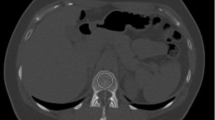

In QCT the BMD is calculated from the measured CT values using a calibration phantom with inserts of known concentrations of hydroxyapatite or K2HPO4-water mixtures, which during the CT scan is positioned below the subject (simultaneous calibration) [1]. This procedure minimizes differences in BMD values across different CT scanner models. In the case of clinical CT, where such a calibration phantom is not used, three main options are available to assess BMD (Table 2). The first is the use of asynchronous calibration, a technique that separates subject and phantom scans [42, 65]. Depending on the stability of the CT scanner, the calibration phantom can be scanned once weekly or once monthly, for example. The second is called internal calibration as the phantom inserts are replaced by air and body tissues such as subcutaneous adipose tissue or blood (Fig. 3). As shown in Table 2, several internal calibration techniques have been proposed.

The accuracy of internal calibration is shown in Fig. 4. The comparison of techniques was performed using routine clinical CT scans that for research purposes also included a calibration phantom. For comparison, the fourth option shows the accuracy of using identical calibration parameters for all scans, equivalent to applying asynchronous calibration from a single phantom measurement. This procedure requires scanner stability, which was the case in this particular dataset but cannot be universally presumed for other datasets. In another dataset from clinical trials using highly standardized CT protocols, errors were about 50% lower compared to those shown in Fig. 4 [69].